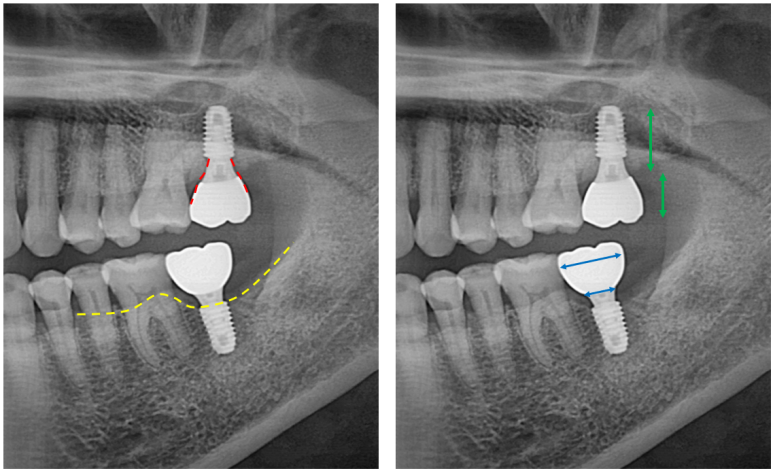

제가 여기서 임플란트 치료 잘 되었는지 확인하는 법을 대략적으로 알려드릴께요!

생각보다 이렇게 제작되어 있는 임플란트가 많지 않습니다. 특히 보다 더 비싼 맞춤형 지대주 (custom abutment)를 사용하지 않고 기성 지대주를 사용하면 이렇게 자연스러운 형태가 되기가 힘듭니다.

주변 뼈 높이에 잘 맞게 임플란트가 심겨있어야 합니다. 너무 깊어도 얕아도 좋지 않죠. 노란색 선이 잇몸뼈 높이를 표시한 것입니다.

임플란트 고정체 (fixture) 그리고 나머지의 비율이 1:1이 넘어가지 않는게 좋습니다. 너무 얕은 땅에 긴 전봇대가 심겨있다고 생각해보시면.. 불안하죠 뭔가?

임플란트 크라운의 중간에 임플란트 고정체가 위치해 있는게 이상적입니다. 상황에 따라 달라질 순 있겠지만, 아무래도 임플란트의 뿌리가 머리의 가운데에 있는게 좋겠죠. 츄파춥스 처럼요.

결론은 어쨌든 임플란트가 아~주 이상적으로 잘 제작되었다는 뜻!